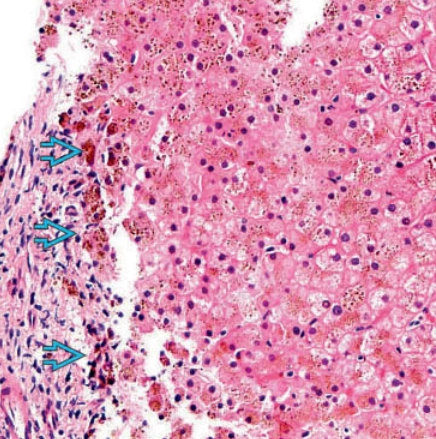

• Gan nhiễm mỡ (Steatotic liver disease)

• Gan nhiễm mỡ khu trú (Focal hepatic steatosis)

• Gan nhiễm mỡ lan tỏa (Diffuse hepatic steatosis)

• Lắng đọng amiodarone trong gan (Amiodarone deposition in the liver)

• Xơ gan (Cirrhosis)

• Gan ứ đọng sắt (Hemochromatosis)

• Gan to (Hepatomegaly)